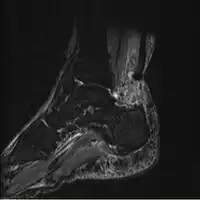

MRI can be used to discern incomplete ruptures from degeneration of the Achilles tendon, and MRI can also distinguish between paratenonitis, tendinosis, and bursitis. This technique uses a strong uniform magnetic field to align millions of protons running through the body. These protons are then bombarded with radio waves that knock some of them out of alignment. When these protons return they emit their own unique radio waves that can be analysed by a computer in 3D to create sharp cross sectional image of the area of interest. MRI can provide unparalleled contrast in soft tissue for an extremely high quality photograph making it easy for technicians to spot tears and other injuries.

Achilles tendon rupture

Transverse plane/Achilles tendon rupture